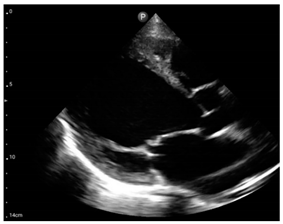

Compared to those who develop HFpEF, clinical HFrEF develops generally through disproportionate myocyte loss rather than hypertrophy (Figure 1) [49].

Figure 1.

Proposed mechanism for the progression of hypertensive heart disease to heart failure patterns, LVH: left ventricular hypertrophy, LV: left ventricular, HFpEF: heart failure with preserved left ventricular ejection fraction, HFrEF: heart failure with reduced left ventricular ejection fraction.